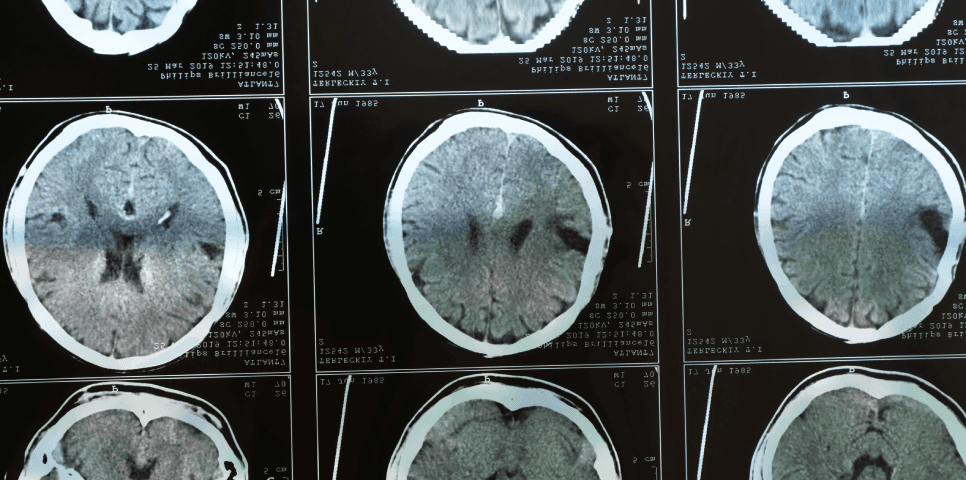

The Consequences of a Traumatic Brain Injury

A traumatic brain injury can leave a victim facing a range of struggles in both the immediate aftermath of their accident and the years that follow. Potential consequences of such an injury include (but aren’t necessarily limited to) the following: